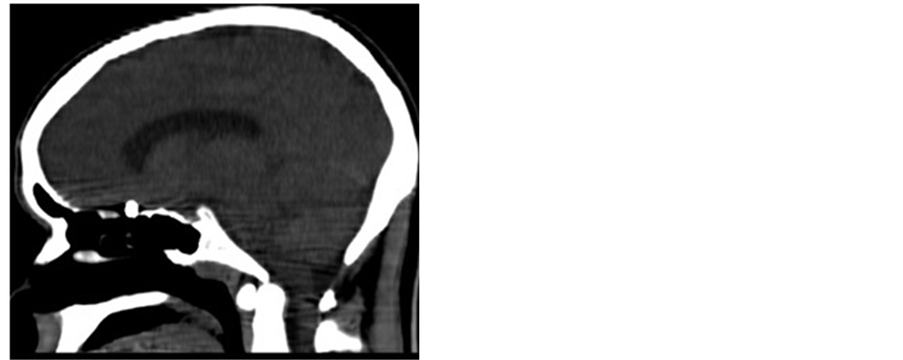

Plain X-rays are adequate to localize metallic fragments. CT is essential to assess soft tissue and bone damage. It is also useful in evaluating the course of the projectile [14] [15] (Figures 1(a)-(c)).

Figure 1. CT scan, sagittal (a, b) and axial (c) views, showing the pellet penetreated to cribriform plate.